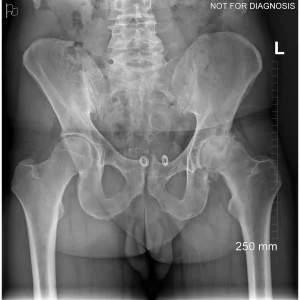

Hip resurfacing is a type of hip surgery used to treat hip arthritis, most commonly in younger and more active patients. Unlike a total hip replacement, hip resurfacing preserves more of your natural thigh bone. Instead of removing the entire femoral head (ball at the top of the thigh bone), the damaged surface is trimmed and covered with a smooth metal cap. The hip’s socket on the pelvis is also fitted with a metal cup.

- Have good bone quality and strong femoral neck bone

- Have minimal deformity of the hip joint

Dr Grammatopoulos will review your X-rays and other imaging carefully to determine whether hip resurfacing is an appropriate option for you.